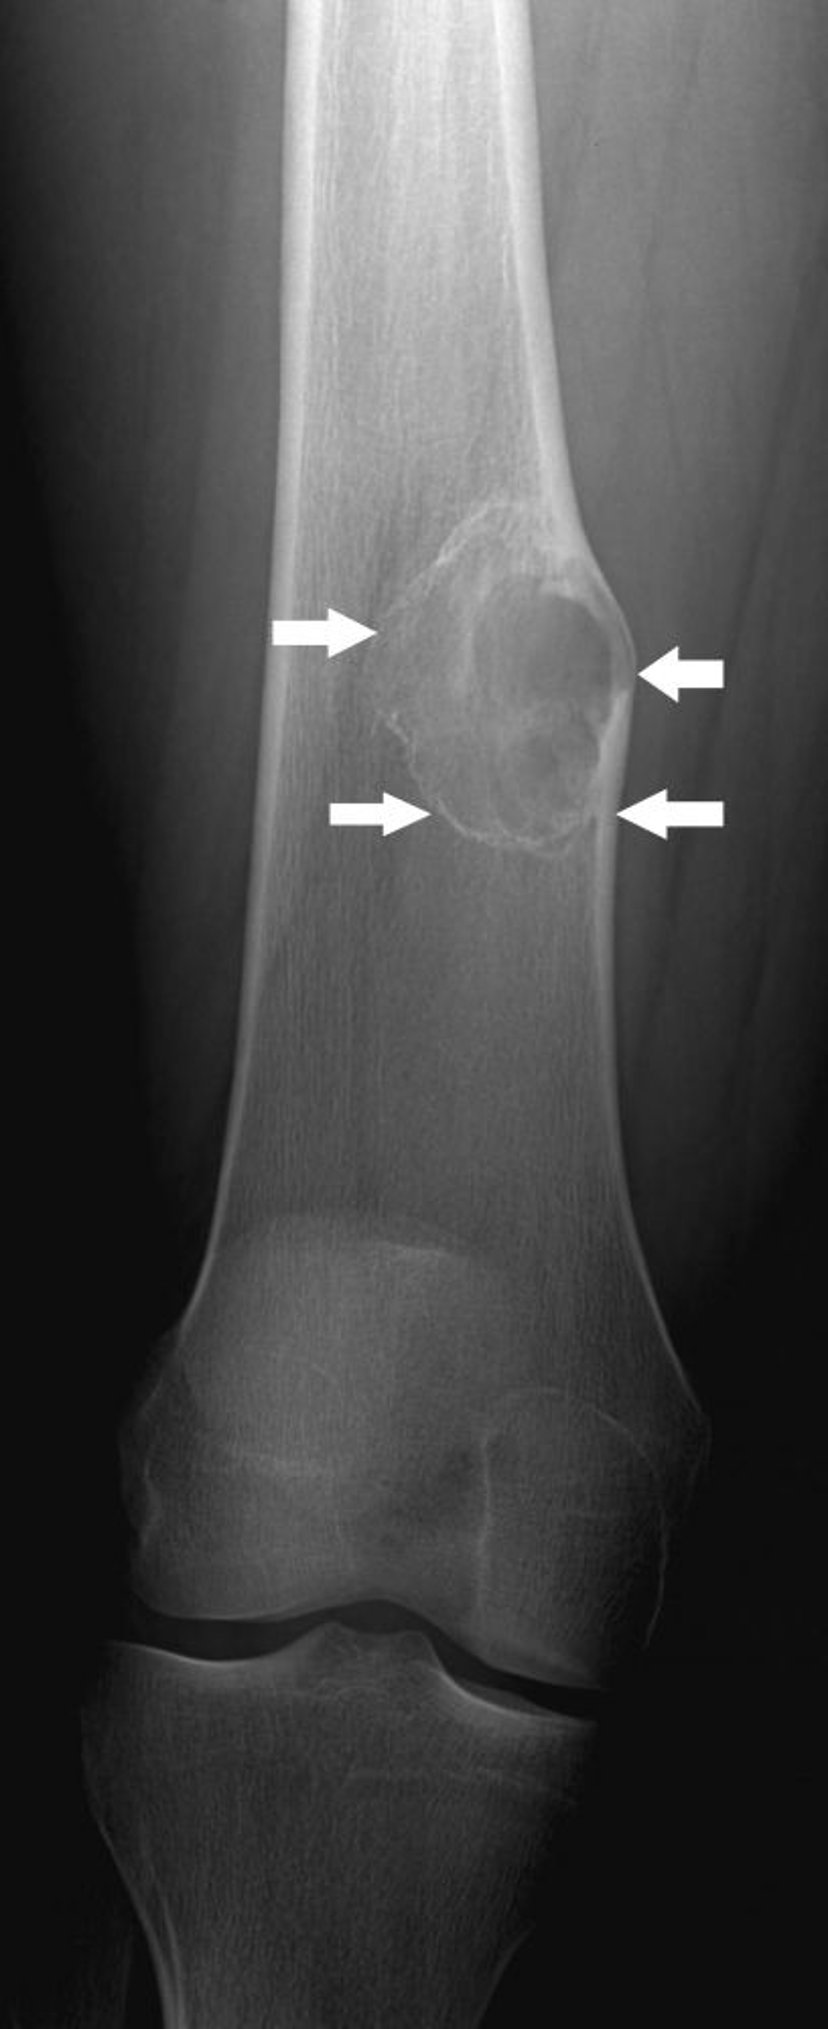

비골화 섬유종

이 X-레이는 무릎 위 허벅지뼈의 비골화 섬유종(화살표)을 보여줍니다.

이미지 제공: Michael J. Joyce, MD 및 Hakan Ilaslan, MD.